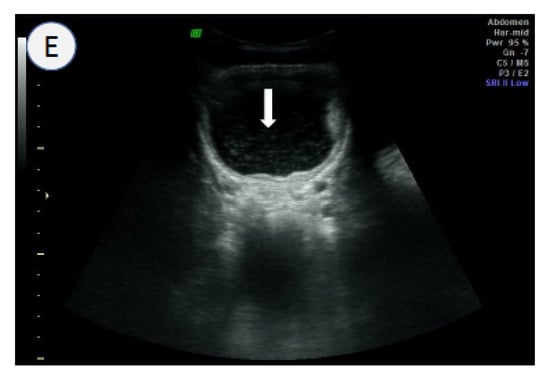

3.4. Ultrasound Scanning

- Kim, M.J.; Hong, S.-T.; Jin, Y.; Ryu, K.; Kim, S.H.; Saeed, A.A.W.; Jeoung, H.G.; Lee, Y.H. Significance of echogenic snow sign as an ultrasonography finding for diagnosis of urogenital schistosomiasis. Am. J. Trop. Med. Hyg. 2016, 95, 842–848. [Google Scholar] [CrossRef]

- Cozzi, D.; Bertelli, E.; Savi, E.; Verna, S.; Zammarchi, L.; Tilli, M.; Rinaldi, F.; Pradella, S.; Agostini, S.; Miele, V. Ultrasound findings in urogenital schistosomiasis: A pictorial essay. J. Ultrasound 2019, 23, 195–205. [Google Scholar] [CrossRef]

| Ultrasound | High sensitivity (>80%) High specificity (>80%) Morbidity information of UGS on site Detection of other co-morbidities | Experienced sonographer Expensive sonograph Feasible for small-scale surveys | Poor Expensive method Feasible with a portable sonograph |